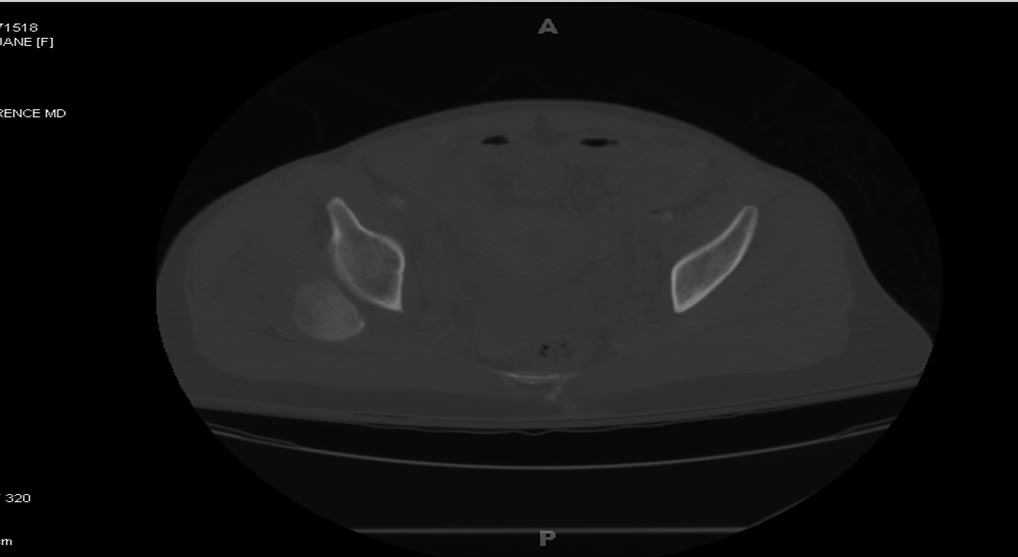

[Ortho] Polytrauma

Вложение не в текстовом формате было извлечено…

Имя     : Picture1.jpg

Тип     : image/jpeg

Размер  : 70367 байтов

Описание: отсутствует

Url     : http://weborto.net:8080/pipermail/ortho/attachments/20180407/cb9d5034/attachment-0010.jpg